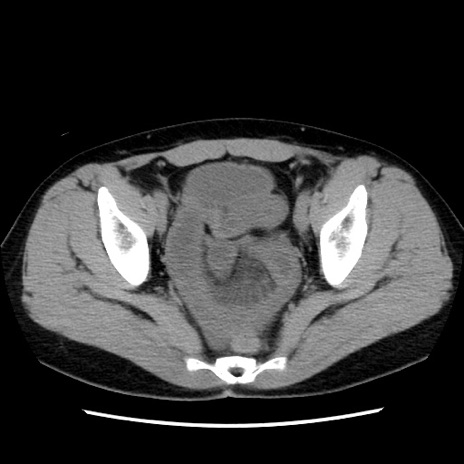

症例10(横断像)

【症例】 50歳代女性

【主訴】 腹痛

【現病歴】前日生レバーを食べた。今朝に排便あり。 昼前に突然発症の腹痛を生じ、当院救急外来を受診した。

【既往歴】 子宮筋腫にてで子宮全摘後

【身体所見】 意識清明、腹部:平坦、軟、下腹部やや左を中心に圧痛・反跳痛あり、筋性防御あり

【データ】WBC 7800、CRP 0.07